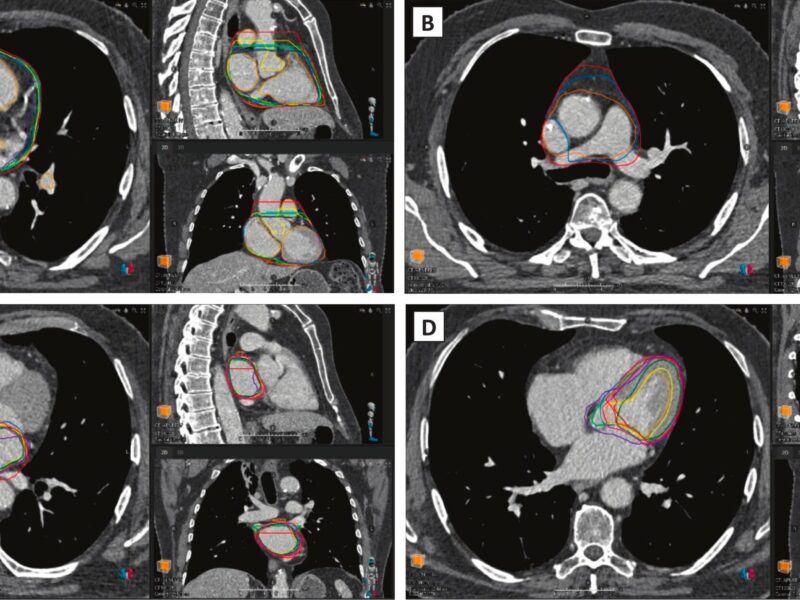

Les logiciels d’IA peinent encore à s’accorder sur les contours du cœur

Des chercheurs de l'Institut de cancérologie de l’ouest, à Saint-Herblain, ont évalué onze solutions d’auto-contourage en imagerie cardiaque. Selon eux, une harmonisation des règles de contouring et la ...